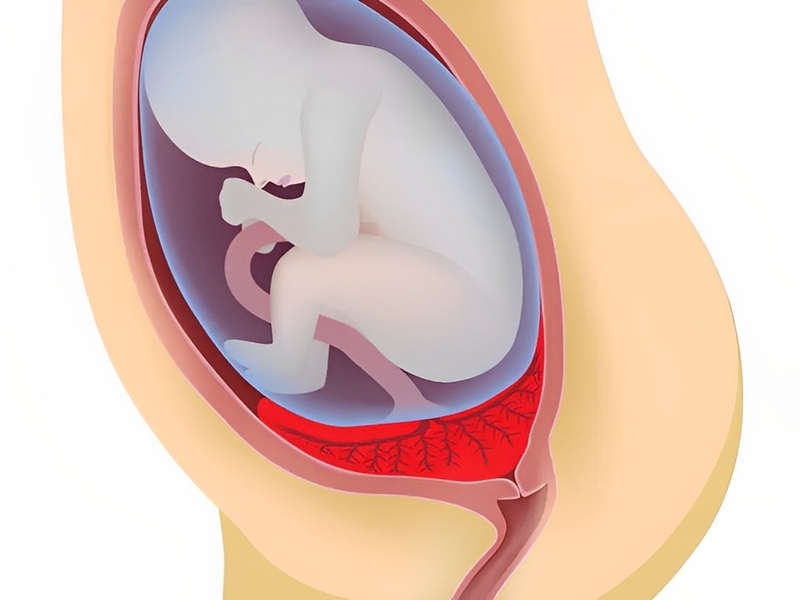

Nhau thai là bộ phận quan trọng có chức năng nối thai nhi với tử cung của mẹ qua dây rốn, từ đó thai nhi có thể phát triển được trong tử cung bằng cách vận chuyển oxy và những chất dinh dưỡng cần thiết để nuôi thai. Đồng thời, nhau thai có vai trò loại bỏ chất thải có hại ra khỏi máu của thai nhi.

Nhau thai trải qua nhiều quá trình thay đổi quan trọng bắt đầu từ khi được thụ thai cho đến lúc sinh ra. Khi thai nhi lớn lên, nhau thai cũng sẽ phát triển để thích ứng với sự phát triển này. Trong giai đoạn cuối của thai kỳ, nhau thai có thể nặng lên tới 500g. Khi đến lúc sinh, tử cung của mẹ sẽ co bóp để đẩy nhau thai ra ngoài. Việc xác định vị trí chính xác của nhau thai là rất quan trọng và có thể quyết định liệu mẹ có thể sinh thường hay phải thực hiện sinh mổ.

Nhau thai bám mặt sau là quá trình khi nhau thai bám vào lớp mô nang buồng trứng thay vì bám vào thành tử cung như bình thường. Điều này xảy ra khi nhau thai không di chuyển xuống tử cung sau khi được thụ thai, mà vẫn ở lại trong ống dẫn trứng.

Loại nhau bám mặt sau nhóm 2 thấp hơn so với nhóm 1, mặc dù đây đều là những vị trí bình thường nhưng vẫn cần phải theo dõi một cách chặt chẽ, bởi khi thai lớn lên, bánh nhau cũng tăng lên về kích thước và diện tích bánh nhau thay đổi, phát triển lan về nhiều phía khác nhau, đặc biệt là nhau bám thấp mặt sau.